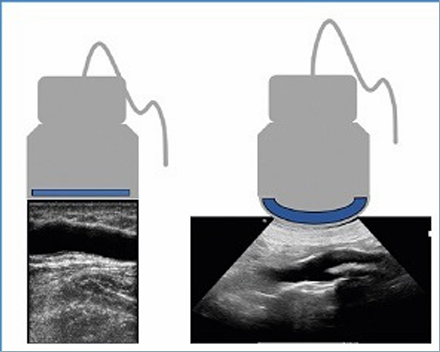

- Sondas microconvex de frecuencias medias-altas

- Sondas lineales frecuencias altas